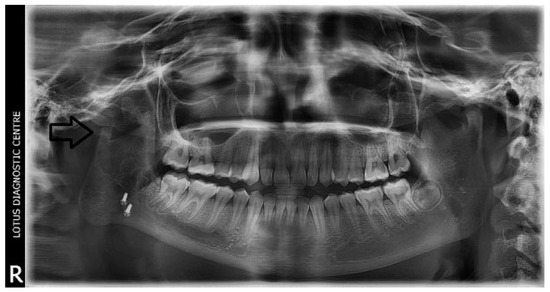

Figure 1. Preoperative OPG of right temporomandibular joint ankylosis.

A retrospective study of post–ankylotic TMJ reconstruction of all the patients who underwent surgery for the TMJ ankylosis over a period of 11 years from 2002 to 2013, which were operated by the senior author (Y.B.), was undertaken to evaluate demographics, type of TMJ ankylosis, and modality of post–ankylotic TMJ reconstruction. The following inclusion criteria were considered for enrolling patients in this study: (1) history of traumatic injury to the face or jaws; (2) clinical and radiographic evidence of bony ankylosis at the time of presentation; (3) reconstruction of the TMJ using autogenous or alloplastic material after surgical release of ankylosis. Patients were assessed for (1) maximum interincisal opening pre and post operatively; (2) restored vertical ramal height; (3) occlusion; (4) facial symmetry; and (5) postoperative complications. Radiographic evaluation consisted of both preoperative and postoperative panoramic radiography Orthopentomogram (OPG) (Figure 1 and Figure 2) and CT scans in axial, coronal, and sagittal sections with three-dimensional reconstruction (Figure 3 and Figure 4). Surgical protocol was that the TMJ was approached through the Al-Kayat and Bramley’s incision and at least 2 to 2.5 cm resection of the ankylotic chunk was performed in all our cases. Ipsilateral and contralateral coronoidectomy was performed when required to achieve passive mouth opening. Interpositional arthroplasty was done using various materials such as temporalis fascia, temporalis muscle, and articular disc, whereas joint reconstruction was done using CCG and titanium reconstruction plate with condylar head. Intensive physiotherapy postoperatively was an integral part of protocol.

The unique ability of the CCG to remodel into neocondyle could be well appreciated on the digital OPG and CT scan of the patient. The length and width of the neocondyle was very much comparable to the length of the condyle on the unaffected side at 6 years follow-up. Thus, the neocondyle formed using the costochondral cartilage was identical to the unaffected mandibular condyle both structurally and functionally. Poor socioeconomic conditions and lack of awareness coupled with poor primary health care facilities lead many of these unfortunate patients to live with this debilitating condition well into adulthood. Five such adult patients with age ranging from 17 to 36 years reported to us for treatment of TMJ ankylosis. In all these patients, ankylotic bony mass extends beyond the boundaries of the joint capsule. Alloplastic reconstruction after the release of ankylosis was our method of treatment, although high cost of condylar prosthesis led us to use 2.4 mm condylar head reconstruction plate along with temporalis muscle interpositioning in these patients. Interpositional grafts may fail to restore the ramal height in bilaterally ankylosed adult patients, so alloplastic condylar reconstruction may become the preferred choice. Advantages of alloplastic TMJ reconstruction are that the physical therapy can begin immediately, there is no need for a secondary donor site, surgery time is decreased, and alloplasts can be constructed in such a way as to mimic the normal anatomic contours of the structures they are to replace [17,18]. Wolford and Karras have suggested autologous fat transplantation as a useful adjunct to prosthetic TMJ reconstruction, as it minimizes the occurrence of excessive joint fibrosis, heterotopic calcification, and improves the range of motion [19]. However, they have categorically stated in their discussion that heterotopic bone formation is seen in multiple operated joints and joints with previously failed alloplastic implants. Another method to combat heterotopic bone formation is the use of 10 Gy of irradiation in five fractionated daily doses in the immediate postoperative period [20]. In our series, none of the patients reported with heterotopic bone formation possibly because they had undergone a single surgical procedure for managing TMJ ankylosis. The risk of fossa perforation could have been taken care by interpositioning of temporalis muscle in all these patients.